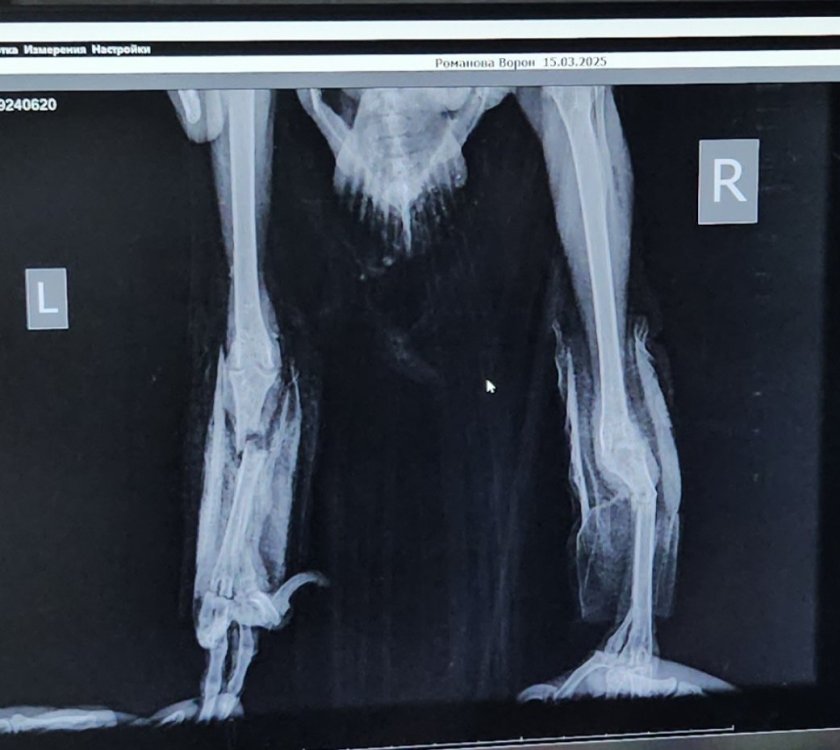

Перелом лапок у ворона,есть ли жизнь для птицы без лапок

Одну лапку сразу убрали,вторую пытались спасти,спица ,но он сам её расколупал, под удаление . Нашли на улице под машиной,около года,ворон или ворона непонятно.

@РамановаНастя воротник надо было надевать, они кольца снимают. Хорошо бы спасти хоть одну лапу....Культи, теоретически да, смотря сколько останется кости, можно что-то типа протезов....

Здравствуйте, нашли поздно, у него и грудина стесана,как получил такую травму неизвестно.к сожалению и вторая под удаление,не прижилась, отсыхать стала. Птиц недержала никогда,желающих или знающих,  что с ним делать,тоже не нашлось. Чем лучше кормить? Нам только мясо сказали,сердце говяжье,хотя они ж всеядны, но аппетит не очень